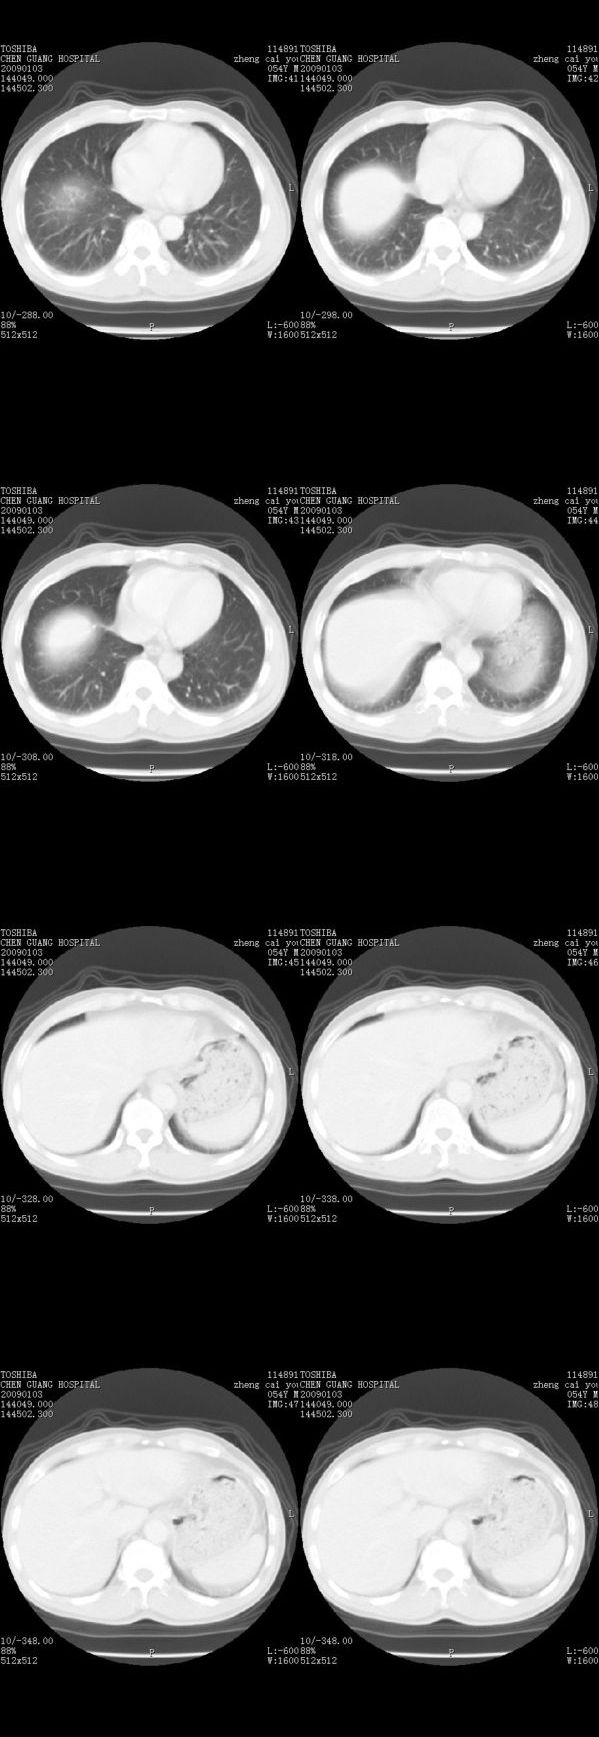

男,54岁,平时有吸烟后咳嗽、咯痰史,因右侧胸部(腋窝下)疼痛来检查平片,见右下肺动脉干起始处处结节,后到同学处做了平扫及增强。请各位老师帮忙看一下,不甚感谢!!!!!

支气管壁增厚

右肺下叶支气管扩张。

顺序确实有点乱,不过在右肺上叶后段近气管旁仍可见一结节灶,希望楼主小心观察分析。

考虑------支气管壁增厚---局限性气肿---建议----气管镜进一步检查

小叶中心型肺气肿

增强了 但纵隔窗调的看不清  右上叶支气管壁似有增厚 警惕

肺窗薄扫、常规扫描均未见明确病变;右下肺门圆形与肺血管等密度影,考虑为血管变异;应该要纵隔窗才能进一步明辨。

主要应该看一下纵隔窗,感觉到右肺门的血管有局限性的扩张,呈结节状,再做个增强ct扫描.

右肺上叶前后段支气管夹角处可见一结节影,图像资料不全,不好下结论。